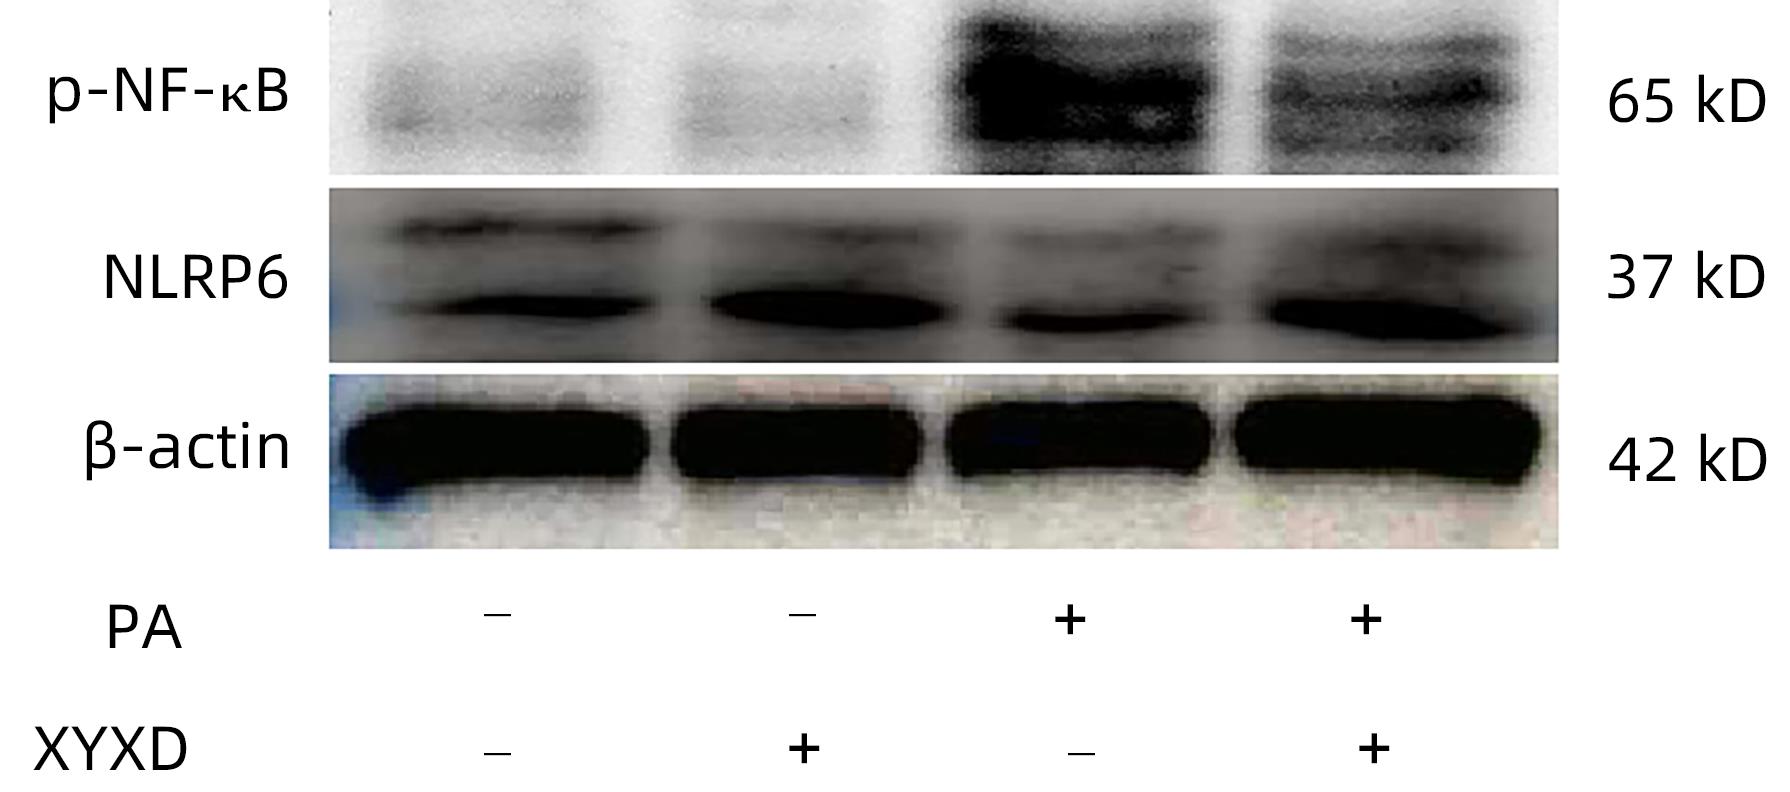

Therapeutic effect of Xiayuxue decoction on a mouse model of nonalcoholic fatty liver disease induced by high-fat diet and its mechanism

Linqi HOU, Zhiyi WANG, Xin ZHAO, Jie ZHANG, Wenting MA, Xuling LIU, Wei ZHANG, Le TAO, Cheng LIU, Liu WU

2024, 40(4): 712-719. DOI: 10.12449/JCH240412

Abstract(1553) HTML (453) PDF (2184KB)(95)

Abstract:

Objective  To investigate the mechanism of action of Xiayuxue decoction in inhibiting nonalcoholic fatty liver disease (NAFLD) induced by high-fat diet in mice by regulating nucleotide binding oligomerization domain like receptor containing pyrin domain protein 6 (NLRP6).  Methods  A total of 15 male C57BL/6 mice were randomly divided into low-fat diet (LFD) group, high-fat diet (HFD) group, and Xiayuxue decoction-HFD group (XYXD group), with 5 mice in each group. Liver function parameters (alanine aminotransferase [ALT] and aspartate aminotransferase [AST]) and blood lipid metabolic indicators (triglycerides [TG] and total cholesterol [TC]) were measured; HE staining and oil red O staining were performed for liver tissue to observe histomorpholoty and lipid droplet deposition; quantitative real-time PCR was used to measure the expression levels of inflammatory factors (tumor necrosis factor-α [TNF-α], interleukin-1β [IL-1β], interleukin-18 [IL-18], and NLRP6) in liver tissue; Western blot was used to measure the protein expression levels of NLRP6, nuclear factor-kappa B (NF-κB), and NF-κB p65; immunohistochemistry was used to measure the expression of NLRP6 and CD68. Mouse Raw264.7 cells were treated with palmitic acid (PA), lipopolysaccharide, and serum containing Xiayuxue decoction to observe inflammation. A one-way analysis of variance was used for comparison of continuous data between multiple groups, and the least significant difference t-test was used for further comparison between two groups.  Results  Compared with the LFD group, the HFD group had significant increases in the serum levels of ALT, AST, TC, and TG (all P<0.05). Liver histopathological examination showed that the HFD group had marked hepatic steatosis and a signficant increase in NAS score (P<0.05), and quantitative real-time PCR showed significant increases in the inflammatory factors such as IL1β and IL-18 and a significant reduction in the expression of NLRP6 (all P<0.05). Immunohistochemistry showed that the expression of NLRP6 showed a similar trend as that of the macrophage marker CD68. Western blot showed that after the downregulation of NLRP6 expression, there was a significant increase in phosphorylated NF-κB p65 (P<0.05). Compared with the HFD group, Xiayuxue decoction effectively improved liver inflammation, upregulated the expression of NLRP6, and downregulated phosphorylated NF-κB p65 in HFD mice (all P<0.05). After Raw264.7 cells were treated with PA, NLRP6 was downregulated to promote the progression of inflammation (P<0.05), and treatment with Xiayuxue decoction could upregulate NLRP6 and inhibit inflammation NF-κB (P<0.05).  Conclusion  Xiayuxue decoction can effectively improve hepatic steatosis and liver inflammation in a mouse model of NAFLD, possibly by regulating NLRP6/NF-κB to alleviate macrophage activation.